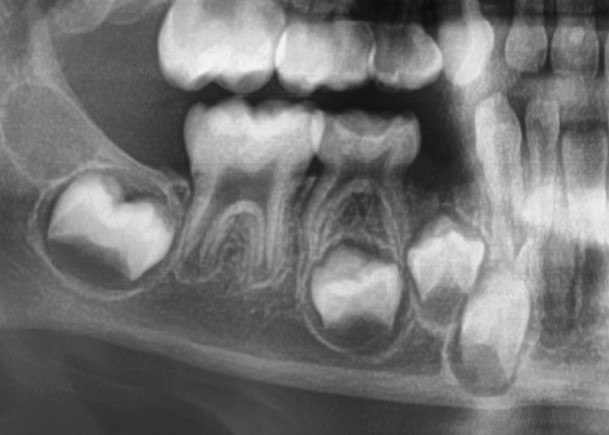

На этом рентгеновском снимке челюсти

Так выглядят молочные зубы ребёнка. Да, они тоже имеют корни, которые по мере роста зачатка постоянных зубов растворяются, из-за чего молочный зуб и выпадает.

На этом фото можно заметить пористую и рыхлую структуру дентина, а также малую толщину эмали молочных зубов